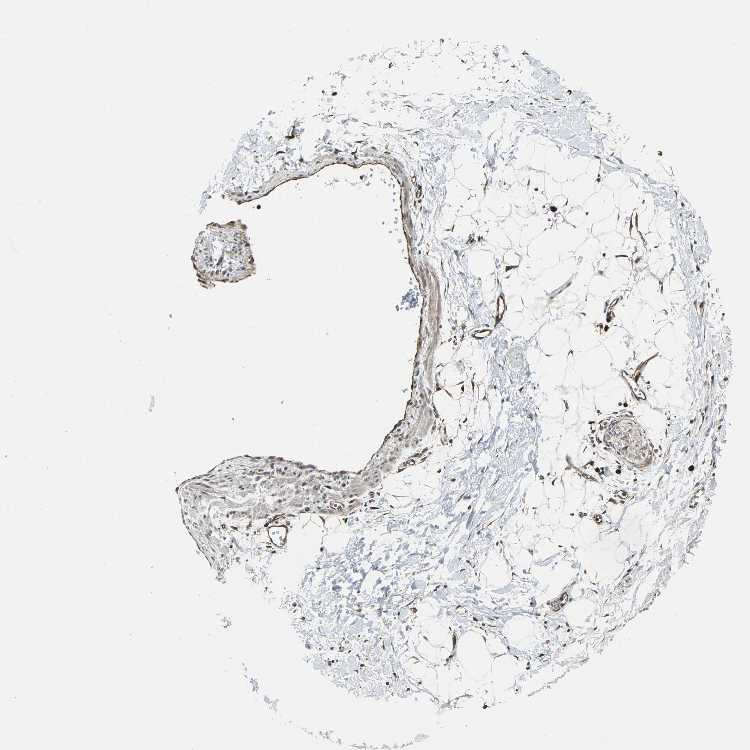

SOFT TISSUE 1 - Antibody stainingi

Antibody staining in the annotated cell types in the current human tissue is reported as not detected, low, medium, or high, based on conventional immunohistochemistry profiling in selected tissues. This score is based on the combination of the staining intensity and fraction of stained cells.

Each image is clickable and will lead to virtual microscopy that enables deeper exploration of all samples and also displays staining intensity scores, fraction scores and subcellular localization as well as patient and tissue information for each sample.

Antibody HPA006616

Fibroblasts Medium

Peripheral nerve Medium